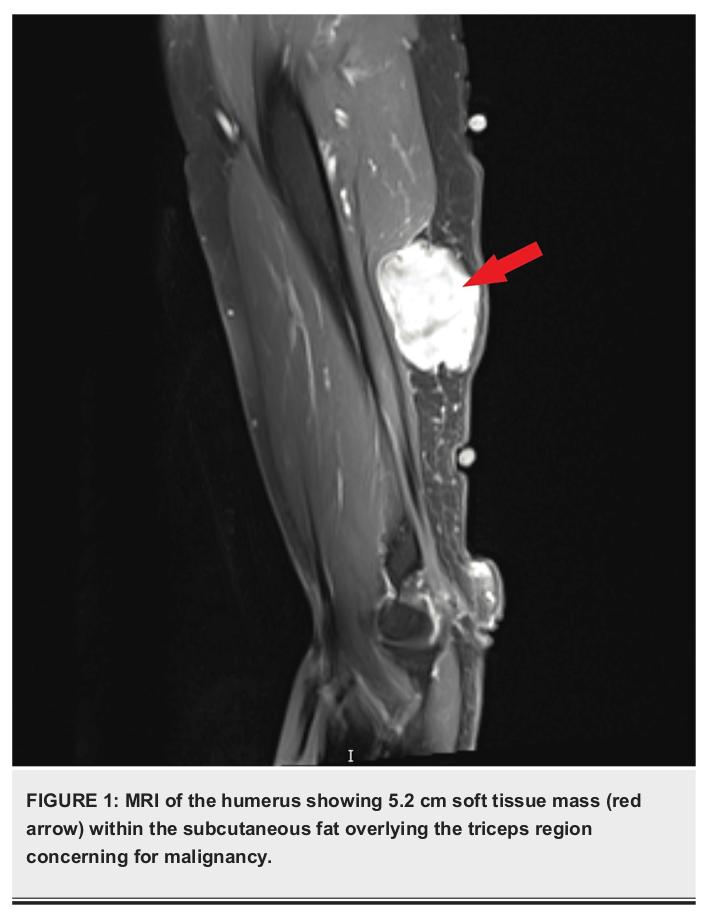

Bae et al 2023 reported on a 73-year-old female with a past medical history of hypertension, hyperlipidemia, and surgery for a benign kidney tumor. She presented with worsening right upper arm swelling, which began two to four days after receiving her second dose of the Moderna vaxxxine. MRI revealed a 5.2 cm soft tissue mass overlying the triceps region, further examination of which led to a diagnosis of high-grade sarcoma (sarcomas are cancers that start in connective tissues such as bone, cartilage, muscle, fat, or vascular tissues). The mass was surgically removed (resected) four months after the initial visit.